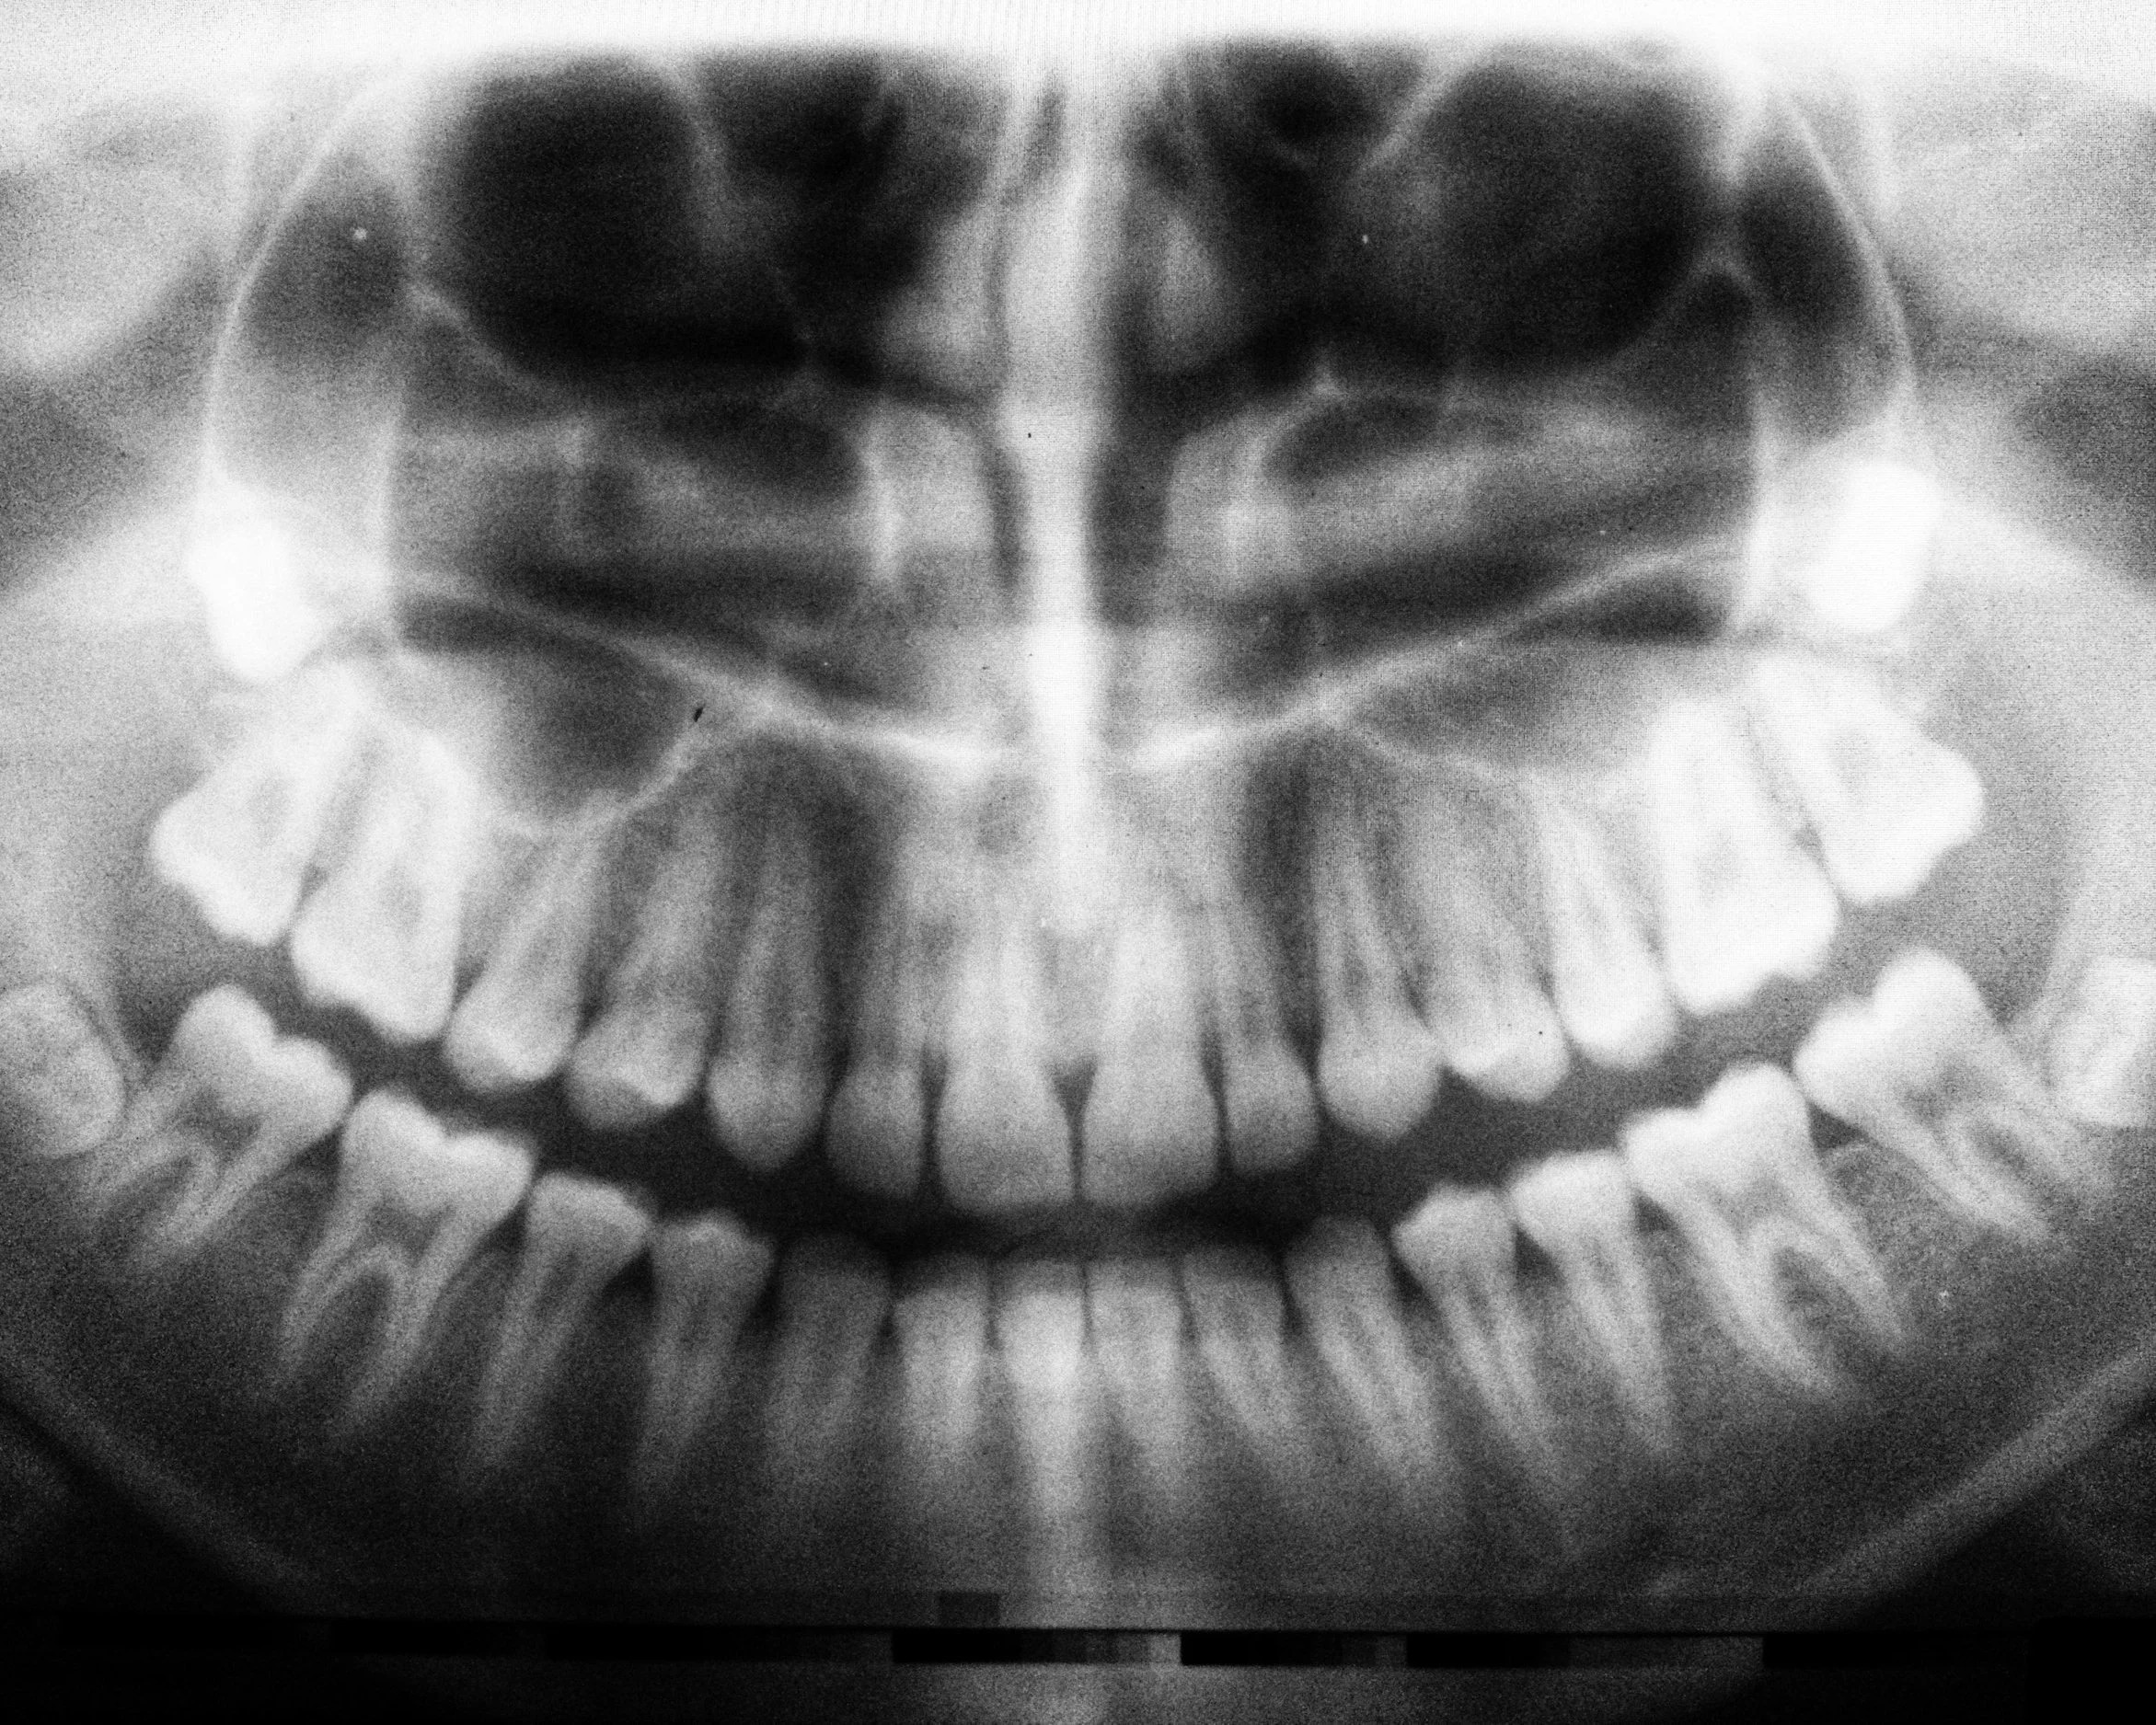

Consultation and X-rays — We take digital X-rays to assess the position and complexity of your wisdom teeth and plan the best approach.